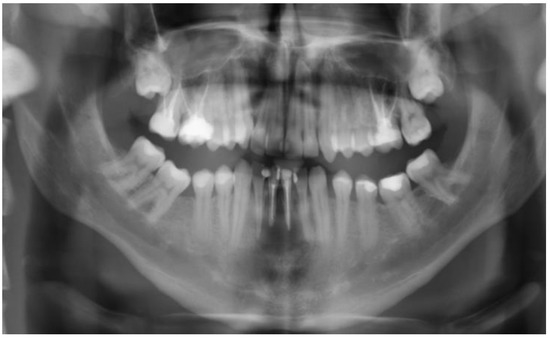

2. Case Description

3. Clinical Procedure and Outcome